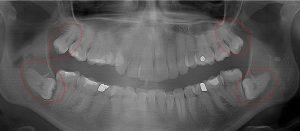

This 34 year old patient has all four third molars present (circled) and fully erupted into occlusion. They appear disease free…but are difficult to keep clean. 3rd molars are the most likely teeth to decay or have gum disease with a >98% probability that decay and gum disease will occur around all four teeth over this patient’s life time.